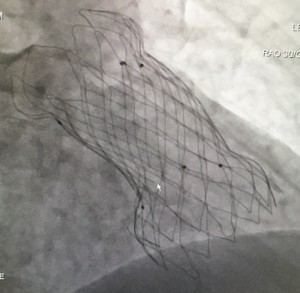

テーマ: Venus P Valveのステント損傷(stent fracture: SF)発生率と要因に関して

これまでの報告の多くはホモグラフトやゴアテックス等による人工導管に対する治療結果で、今回、私の研究対象とするデバイスはVenus P Valve (8)という自己拡張型肺動脈弁デバイスで、これまでカテーテルでは治療が困難であった、高度に拡張した自己右室流出路(主に自己肺動脈弁温存術後症例)が対象となり、これまでの研究結果とは異なったデータ蓄積となります。

現在Venus P Valveの国際共同研究が進行中で、全症例に術前、術中、治療後6ヶ月時の透視撮影が行われています。その内の当院の症例からSFの発生率と、その原因について調査しています。研究のなかでは特に、右室流出路の心拍変動による影響に注目しています。PCIの領域でもhinge motion部など心拍による動きの大きい部位はSFが憂慮されますが、右室流出路も同様で収縮期、拡張期の変化や伸展、屈曲が大きい部分です。TAVIのSF率の低さと比較すると、左室流出路(大動脈弁)と右室流出路(肺動脈弁)の構造的な違いは明らかです。

症例の蓄積、フォローアップが進行中ですので、詳細は報告できない現状にありますが、現在までのデータに限定すると、術前の右室流出路計に比較して大きいサイズのデバイス使用と、拍動による短軸方向の収縮が大きい症例にSFが多い傾向があることが示されています。またSFはほぼ全ての症例で右室側にあたるステント下端部に発生しています。今後症例が揃えば、デバイスサイズ選択やSFの予測に有用な情報になるのではと期待しています。